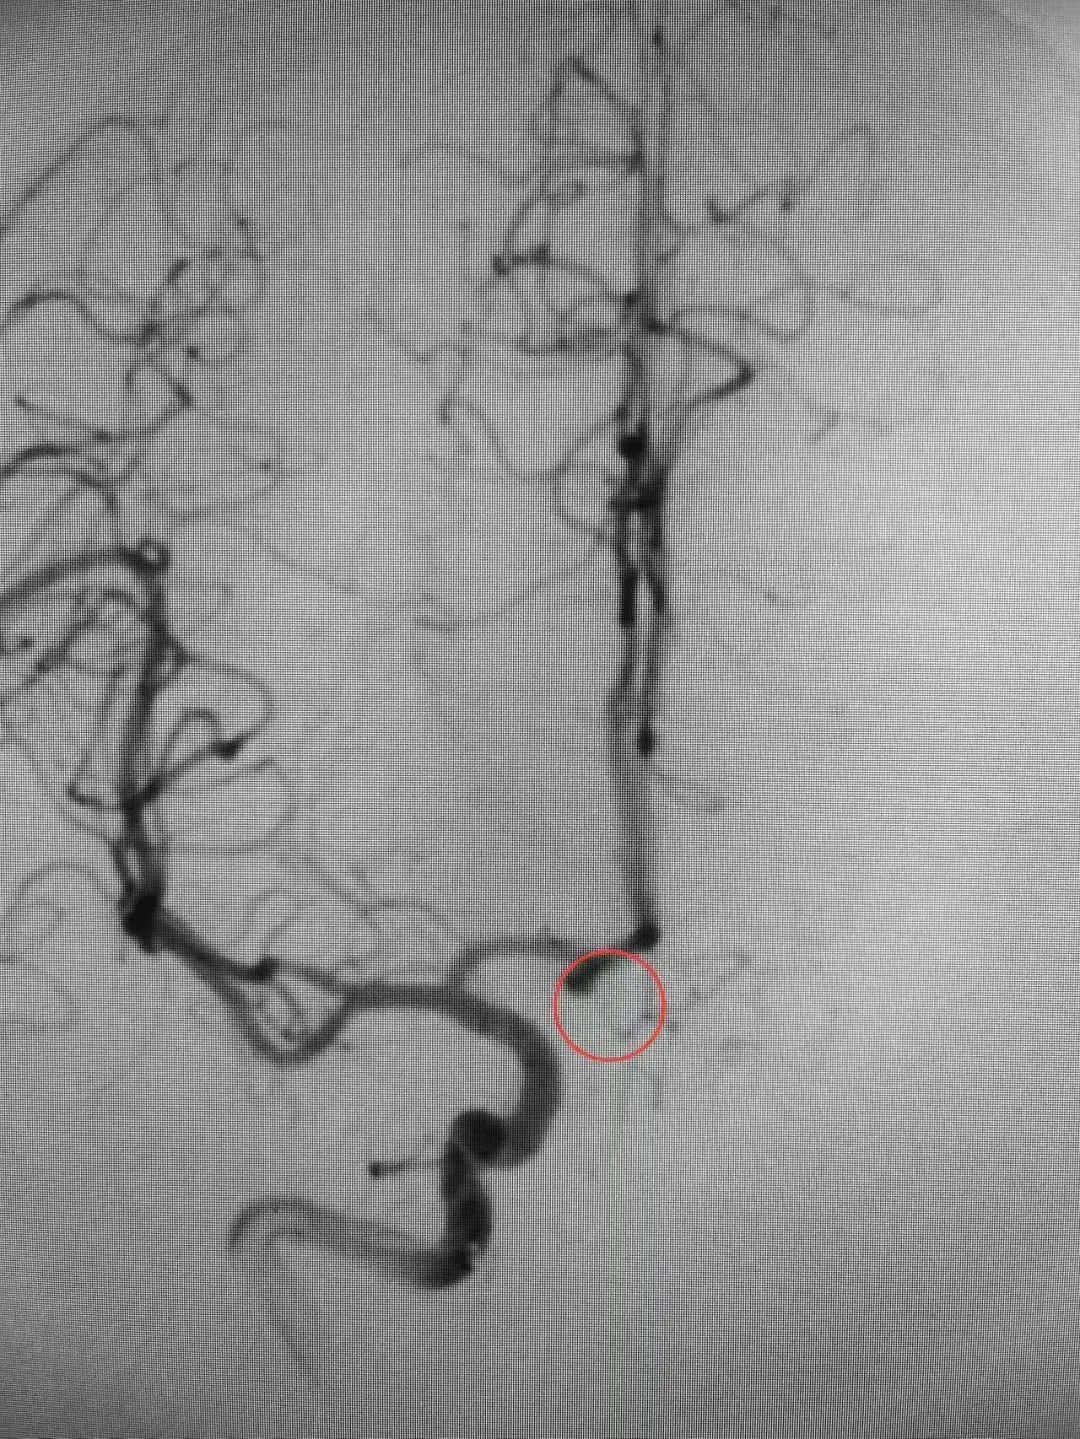

近日,殷女士在家中突发头痛,随后意识丧失,被家人送至幸运轮盘娱乐中心 急诊科。医生迅速安排颅脑CT扫描等相关检查。结果显示蛛网膜下腔出血,CTA显示前交通动脉瘤。情况紧急,幸运轮盘娱乐中心 脑病科过智伟医生考虑殷女士此次发病与动脉瘤破裂有关,前交通动脉瘤破裂死亡率高达30-40%,死亡风险高,需立即手术处理。在与殷女士家属进行充分沟通,详细解释了病情和治疗方案后,医护团队立即实施了急诊局麻下全脑血管造影+全麻颅内动脉瘤栓塞术。手术造影过程中,发现造影剂外渗,动脉瘤仍在持续出血,死亡率随之提高。医护团队沉着冷静,最终成功排除了殷女士脑中的这颗“不定时炸弹”。

△术前△ △术后△